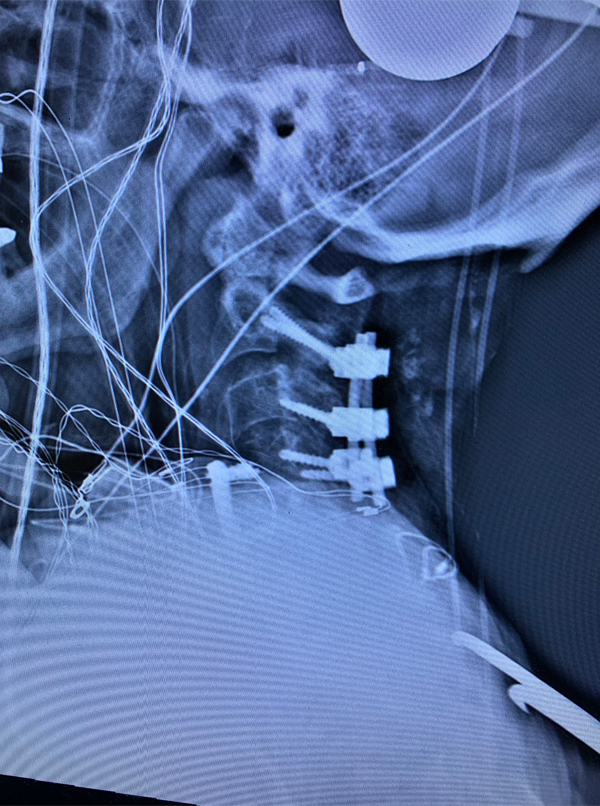

An MRI (Fig. 1) demonstrated severe stenosis at C2-3 with cord compression secondary to significant thickened posterior ligament and facet arthropathy. The patient had a posterior cervical laminectomy C1-3 to decompress the spinal cord and instrumented fusion C2-4.On exploration, the patient was deemed to be fused and the previous hardware was removed except for the lateral mass screws at C3 and C4 were left in. Postoperatively the patient had an uneventful course with some improvement in finger extensor strength.

Figure 3: Postoperative lateral c-spine x-ray showing removal of prior long posterior construct with final short segment fusion C2-C4. Note addition of bilateral C2 pars screws.